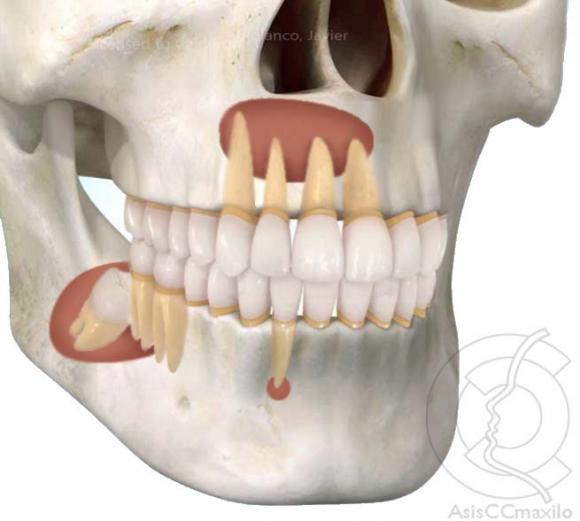

Patólogos y odontólogos de la Universidad de Iowa buscan mostrar las diferencias entre algunos casos de simple curación y otros reincidentes que requieren tratamiento adicional especial.

En una entrevista en la casa de estudios, los autores, el profesor de patología, Robert Robinson, de la Escuela de Medicina Carver y el profesor Steven Vincent, jefe de patología oral de la Facultad de Odontología de la Universidad de Iowa, explicaron que la mayoría de los tumores de la mandíbula tienen condiciones similares a los otros tumores óseos.

Sin embargo aclararon que “hay tumores y quistes en la mandíbula superior e inferior que no se encuentran en ningún otro lugar y tienen características clínicas y microscópicas únicas”.

Los patólogos sugieren que algunos de estos requieren seguir un tratamiento especial adicional para evitar que reincidan y se formen nuevamente. Esto obliga a los odontólogos y especialistas a saber diferenciarlos de aquellos que pueden ser tratados de una manera muy simple.